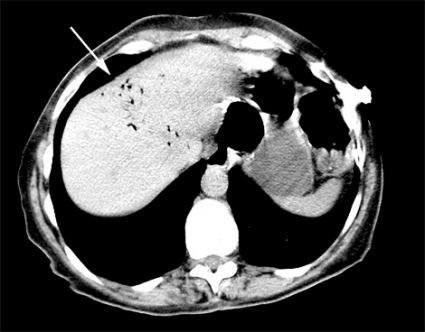

Patienten hade en grymtande spontanandning, vilken förbättrades genom extension i nacken. Patienten låg i vänster sidoläge, tippades i Trendelenburgläge och fick 10 liter syrgas på mask. I enlighet med våra rutiner vid plötslig medvetslöshet utlöstes hjärtlarm, och kardiolog och intensivvårdsteam anlände. Datortomografi (DT) av skallen genomföres under frågeställningen blödning, av torax under frågeställningen aspiration och av buken under frågeställningen fri gas. I det preliminära röntgenutlåtandet sågs rikligt med gas i tarmlumen och även intrahepatisk gas, sannolikt belägen i gallvägarna (Figur 2). Ingen cerebral infarkt eller blödning noterades. Patienten fördes till neurointensivvårdsavdelning och undersöktes av neurolog, som primärt misstänkte status epilepticus, men akut elektroencefalografi visade ingen epileptisk aktivitet.

Vid litteratursökning senare samma dag återfanns ett mycket snarlikt fall av cerebral luftembolisering [1]. DT-undersökningarna granskades på nytt. Som tidigare nämnts fanns luft intrahepatiskt, men den här gången noterades luft även i vena femoralis på höger sida (Figur 2) samt i mindre kärl i glutealregionen på höger sida och i båda sidors ovarikakärl. Misstanke fanns även om luft i mesenterialkärlen. På DT av skallen återfanns intrakraniellt belägen luft i flera kärl, främst parietooccipitalt på vänster sida (Figur 3) men även högt frontalt bilateralt.